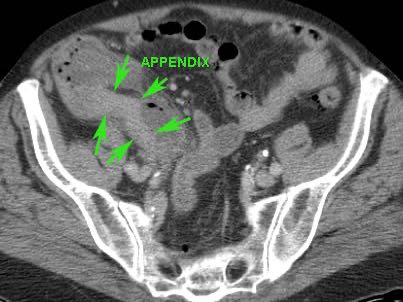

Ở người phụ nữ 56 tuổi này với CRP 180, siêu âm phát hiện dịch trong phúc mạc đục (*) và có thể thấy ruột thừa viêm với sỏi phân (mũi tên).

CT xác nhận hai sỏi phân ở hố chậu phải với hình ảnh khí bất thường, nghi ngờ viêm ruột thừa thủng.

Chọc hút dưới hướng dẫn siêu âm xác nhận dịch mủ.

Phẫu thuật cấp cứu phát hiện viêm ruột thừa thủng với nhiễm bẩn mủ bốn góc phần tư ổ bụng.